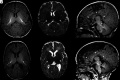

Fig 1.

Typical MR imaging brain appearances of term-born and preterm infants, at TEA. Axial T1-(A) and T2- (B) and sagittal T1 (C)-weighted images of a term-born infant (40 weeks’ gestational age) imaged at 44 weeks PMA. Note the high-T1/low-T2 signal within the PLIC from the myelin (arrows, A and B); the complex cortical folding; small, symmetric ventricles; and the typical appearance of a normal corpus callosum (arrowheads, C). By comparison, D–F are comparable images obtained from an infant born at 25 + 2 weeks’ gestational age and imaged at 42 + 4 weeks’ PMA. This infant had no acquired focal lesions however, note the scaphocephaly, reduced cortical folding, globally thinned corpus callosum (arrowheads, F), mildly dilated ventricles, and diffuse high-T2/low-T1 signal in the white matter compared with the term infant. There is grossly normal myelination in the PLIC (arrows, D and E).